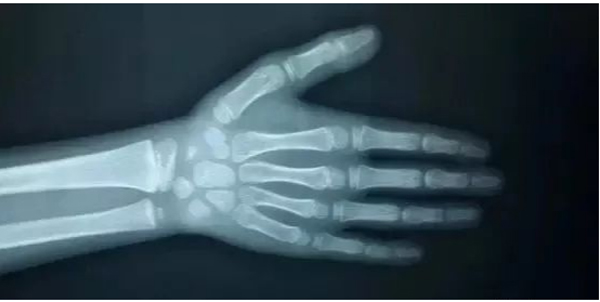

什么是骨龄?

骨龄是骨骼年龄的简称,它是以小儿骨骼实际发育程度同标准发育程度进行比较,所求得的一个发育年龄。

骨龄在很大程度上代表了孩子真实的发育水平,相对于年龄、身高、体重,骨龄其实更能反映孩子真正的发育水平与身体成熟程度。

骨龄用以判断孩子是否与生物年龄相同,是否偏离正常的生长发育,以及身高增长空间还有多少。除此之外,还能提示孩子有没有内分泌、营养障碍等问题,因此用骨龄来判定人体成熟度比实际年龄更为确切。例如:男孩年龄10岁,但骨龄是12岁,说明发育速度较快,身体生理发育水平已经达到了12岁;若骨龄是8岁,说明他的发育速度较慢,只发育到了正常孩子8岁的水平。